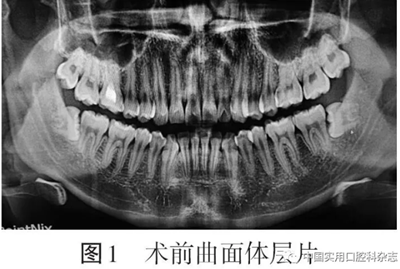

患者男,24歲,以“雙側(cè)下頜智齒拔除術(shù)后2 d伴胸痛”為主訴于2019-12-25來(lái)北京大學(xué)口腔醫(yī)院口腔頜面外科就診?;颊咦允? d前拍攝曲面體層片發(fā)現(xiàn)雙側(cè)下頜第三磨牙阻生(圖1)

否認(rèn)反復(fù)牙齦腫痛病史,于外院拔除雙側(cè)下頜第三磨牙,局部麻醉后使用“高速渦輪機(jī)分牙拔除”,手術(shù)時(shí)間約50 min,術(shù)中自覺頸部突發(fā)疼痛、肌肉抽搐,術(shù)后即刻出現(xiàn)胸痛,深呼吸時(shí)疼痛加重。術(shù)后第1天轉(zhuǎn)動(dòng)頸部時(shí)出現(xiàn)氣泡破裂音,偶有頭暈,否認(rèn)發(fā)熱、惡心、心悸、呼吸困難,于外院靜脈輸液“美洛西林舒巴坦5 g(每日2次)、奧硝唑200 mL(每日1次)”1 d,自覺癥狀稍有減輕,于術(shù)后第2天來(lái)我院就診要求進(jìn)一步治療。臨床檢查:雙側(cè)面頰部自眶下至下頜骨下緣、頸部、鎖骨上及胸部輕度腫脹,皮溫不高,皮色不紅,觸診可及捻發(fā)音(圖2)